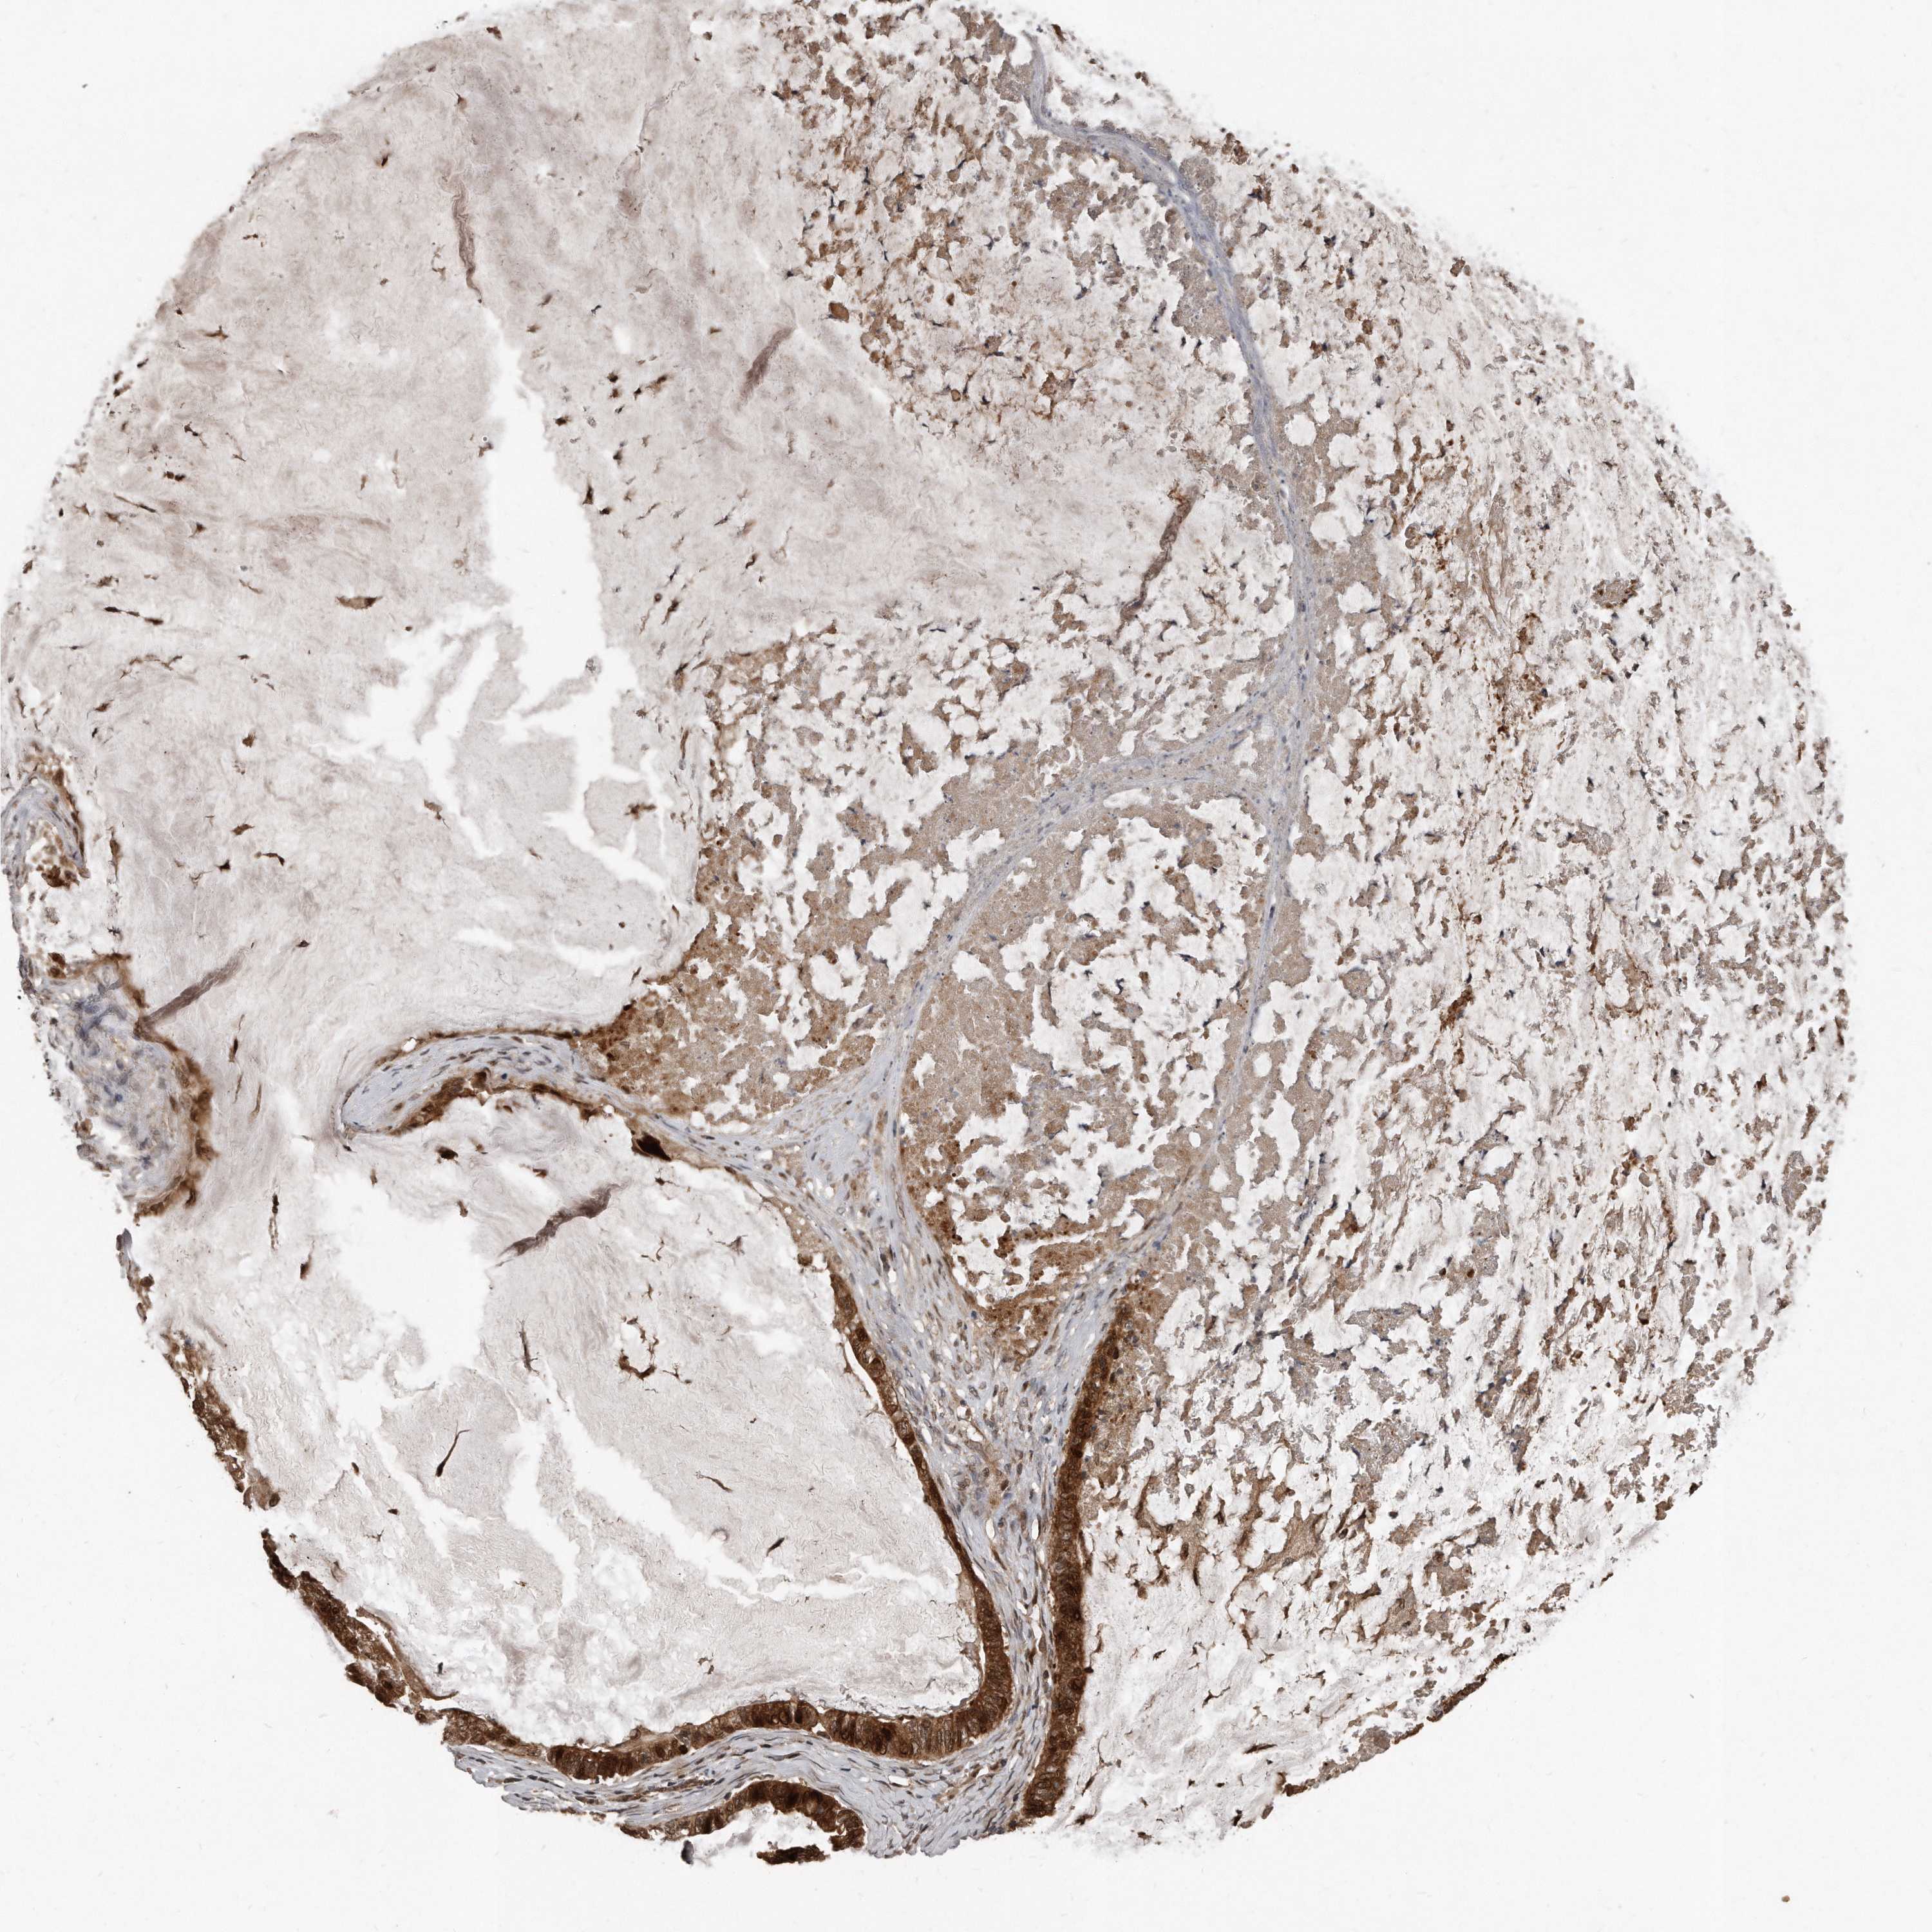

OVARIAN CANCER - Protein expressioni

A mouse-over function shows sample information and annotation data. Click on an image to view it in a full screen mode. Samples can be filtered based on level of antibody staining by selecting one or several of the following categories: high, medium, low and not detected. The assay and annotation is described here.

Note that samples used for immunohistochemistry by the Human Protein Atlas do not correspond to samples in the TCGA dataset.

Antibody stainingi

Antibody staining in the annotated cell types in the current human tissue is reported as not detected, low, medium, or high, based on conventional immunohistochemistry profiling in selected tissues. This score is based on the combination of the staining intensity and fraction of stained cells.

Each image is clickable and will lead to virtual microscopy that enables deeper exploration of all samples and also displays staining intensity scores, fraction scores and subcellular localization as well as patient and tissue information for each sample.

Antibody HPA028612

Staining

High

Medium

Low

Not detected

Intensity

Strong

Moderate

Weak

Negative

Quantity

>75%

75%-25%

<25%

None

Location

Nuclear

Cytoplasmic/membranous

Cytoplasmic/membranous,nuclear

Cystadenocarcinoma, serous, NOS

Carcinoma, endometroid

Cystadenocarcinoma, mucinous, NOS

Carcinoma, NOS